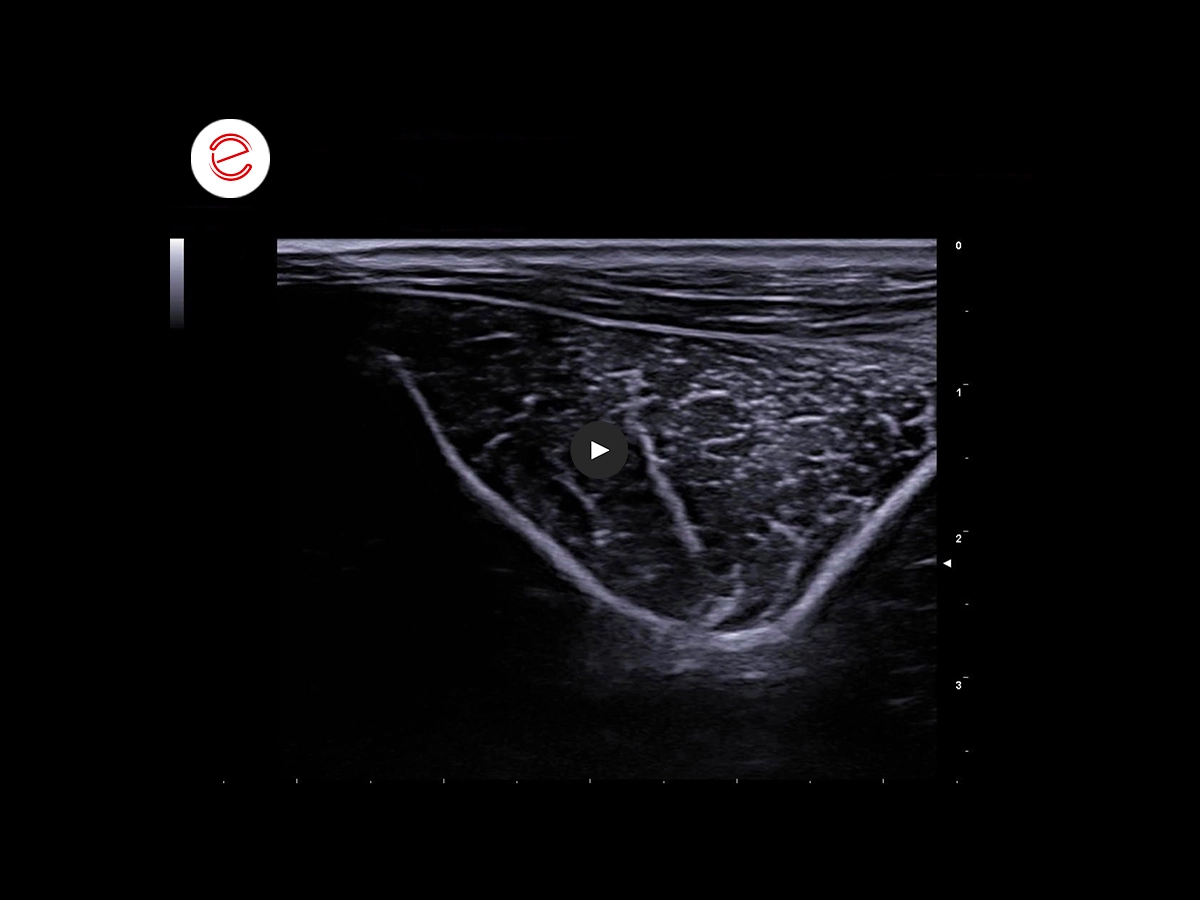

Slight increase in the thickness of the brachial biceps tendon, particularly around the proximal insertion, where it presents a heterogenous echotexture due to the presence of multiple millimetric hyperechogenic foci forming an acoustic shadow over the medial half.

Furthermore, the image shows moderate ectasis of the sheath of the brachial biceps, which is more pronounced around the bicipital groove and the myotendinous junction.